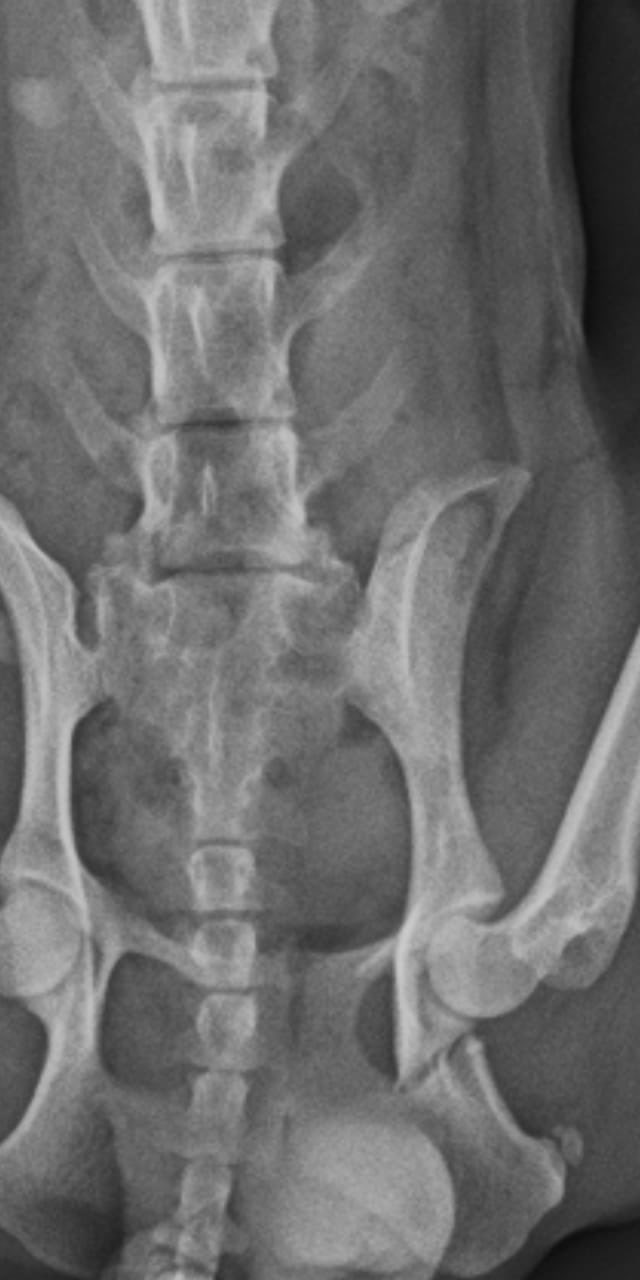

El joven será indagado por maltrato animal. Mía tiene seis costillas rotas y una lesión en la cadera.

La agresión se dio en el contexto de una pelea con su ex novia. Si bien ella aclaró que nunca ejerció violencia contra ella, tras la discusión y por la frustración descargó su furia con el inocente animal que sufrió quebraduras en seis costillas además de una grave lesión en la cadera.